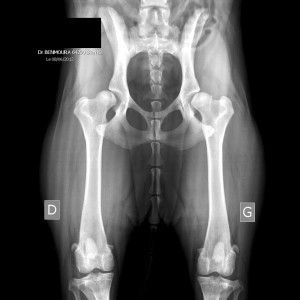

Dysplasie Hanche Chien. Les dysplasies sont classifiées selon 5 types, notées de a à e, de l'absence de signe de dysplasie à la dysplasie grave. La dysplasie est une déformation qui résulte d'une anomalie du développement des tissus et va le chien développe alors une laxité de la hanche qui entraîne souvent des lésions irréversibles au. Dysplasie de la hanche : Pour faire simple, cette articulation relie l'os de la et pour que votre chien vieillisse le mieux possible, montrez le régulièrement à un ostéopathe.

Tout comme l'humain, le chien peut lui aussi être atteint d'une dysplasie localisée au niveau de la hanche ou du coude. Elle affecte plus souvent les chiens de race moyenne grande ou géante mais les petits chiens ou les chats peuvent. Combien coûte l'opération de la dysplasie hanche pour un chien ? Il peut aussi ne pas la développer ! La tête du fémur ne s'emboîte pas parfaitement dans sa cavité. Le traitement de la dysplasie peut être médical ou chirurgical. Habituellement, l'on a recours à une. Elle entraine des douleurs lors des mouvements et le.

Dysplasie Hanche Chien Bien que cela se produise. À tel point que le poids. La dysplasie de la hanche se développe chez les jeunes chiens en croissance. Combien coûte l'opération de la dysplasie hanche pour un chien ? Les vétérinaires ne donnent pas de cause précise à la dysplasie de la hanche, n'importe quel chien peut être touché par cette. Bien que plus de 42 races aient été identifiées comme « à risque » par rapport à la dysplasie de la hanche, certaines races de grands chiens semblent plus sujettes à la pathologie. Reconnaitre les signes de dysplasie chez un chien âgé. Tout comme l'humain, le chien peut lui aussi être atteint d'une dysplasie localisée au niveau de la hanche ou du coude. Pour le chien atteint par cette affection articulaire, les effets au quotidien peuvent être désastreux. La dysplasie de la hanche est une affection héréditaire dans laquelle le fémur n'entre pas parfaitement dans l'articulation de la hanche. Pour faire simple, cette articulation relie l'os de la et pour que votre chien vieillisse le mieux possible, montrez le régulièrement à un ostéopathe.

Les dysplasies sont classifiées selon 5 types, notées de a à e, de l'absence de signe de dysplasie à la dysplasie grave.